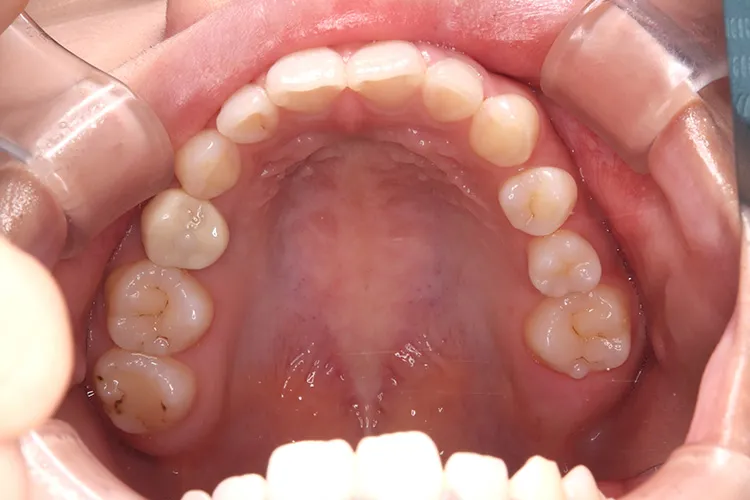

左下の大臼歯の欠損を長期間放置したために上の歯が下がってきてしまい、他の歯医者で被せを入れることができないと断られうちに来られました。下がってきてしまった上の奥歯を部分矯正で上に引っ張り上げ、下に被せ物を入れるスペースを作り、インプラントを入れて噛み合わせを回復しました。部分矯正開始から1年半で治療完了しました。

左下67 欠損に対してインプラント治療を行った症例

部分床義歯を使用していたが、どうしても慣れない上にしっかり噛むことができないためインプラント治療を希望